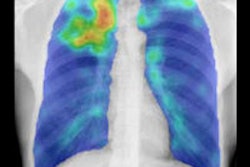

Results showed significant improvement in sensitivity pre- and postnormalization on all three x-ray units. The area under the ROC curve improved from 0.61 to 0.80 on the Atomed DR, from 0.80 to 0.87 on the Odelca DR, and from 0.47 to 0.84 on a Philips Healthcare DR system."After normalization, we see all of the Az values increase -- they are all 0.8 now, which is a nice improvement," Philipsen said.

The application of energy normalization improved CAD's ability to distinguish normal (top row) from abnormal (bottom row) chest radiographs.Energy normalization works well, improving the robustness of the CAD system for tuberculosis, Philipsen concluded. The process "can be used reliably on data from different x-ray units and has great potential in TB screening," he said.